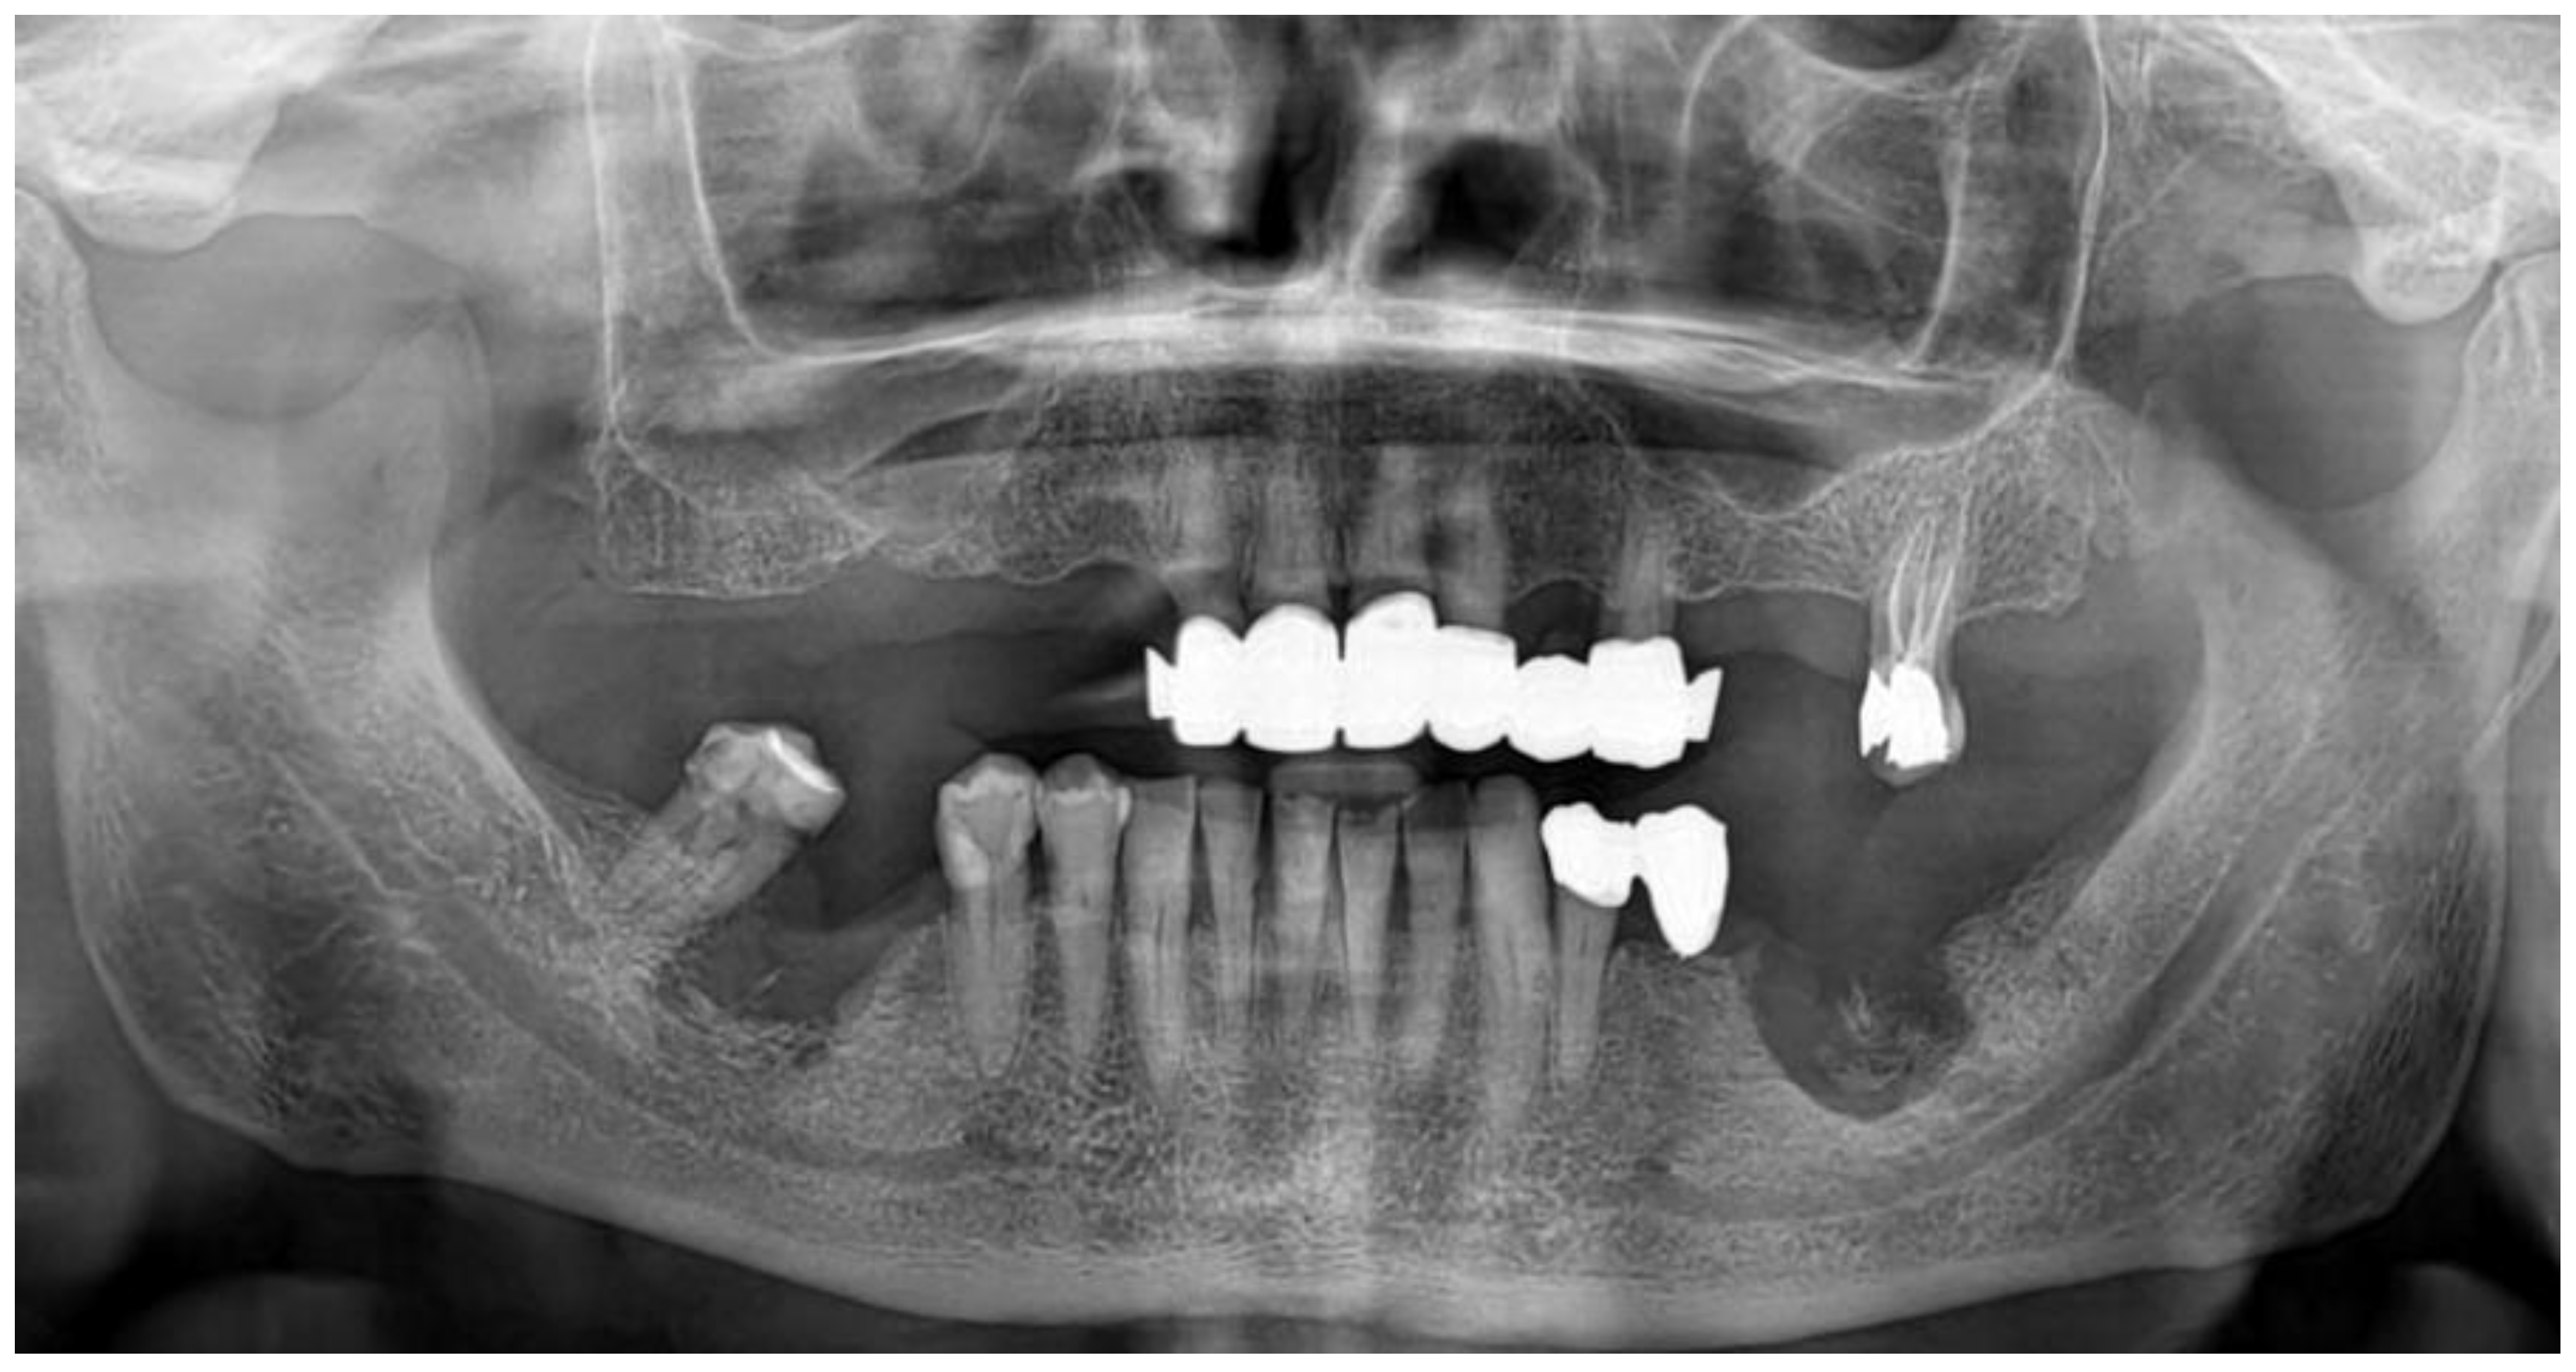

2.1. Case Presentation

- Pre-operative evaluation. The patient undergoes a cone-beam CT exam with a reference plate containing the fiducial markers, fixed on his inferior teeth. The Digital Imaging and Communications in Medicine (DICOM) were imported into the navigation software.